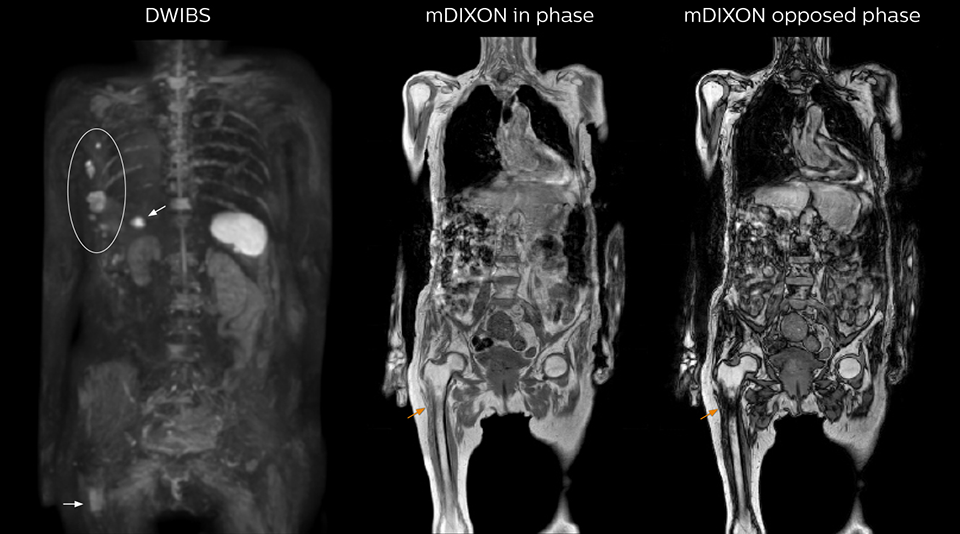

Kawasaki Sawai Hospital’s whole body protocol also includes an mDIXON FFE sequence. Because mDIXON provides images for four contrast types – water only, fat only, in-phase and out-of-phase – from a single acquisition, it is useful in many ways.

“mDIXON FFE allows us to quickly get information we need to assess the presence of fat. That gives us more information when we need to diagnose bone lesions, and when we are asked to judge fat-containing lesions such as hepatocellular or renal carcinoma,” Dr. Nobusawa says.

“The mDIXON fat images can help us to differentiate fatty bone marrow from bone lesions. This is especially useful in elderly people, who tend to have fattier bone marrow. The water images provide a high signal-to-noise ratio in the intestinal canal, which is valuable for visualizing lesions in the colon,” he says.

“In-phase and out-phase sagittal T1-weighted FFE images help us to visualize and further characterize bone lesions such as metastasis and bone-marrow hyperplasia that have high signal on DWI. These images are also used throughout radiotherapy, to monitor changes in the fatty bone marrow.”